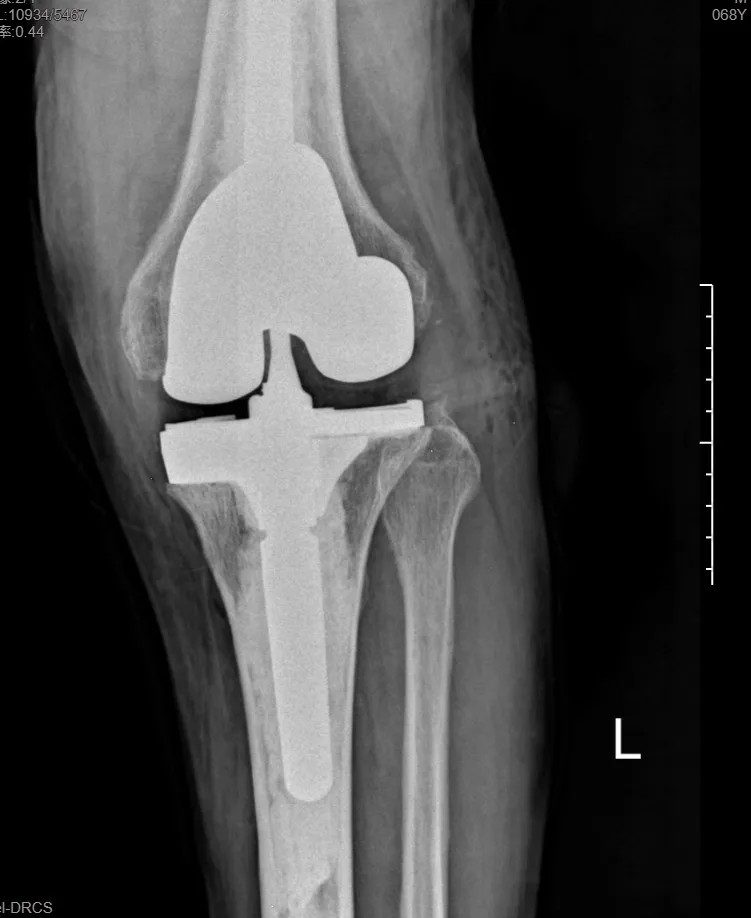

本次手術(shù)的核心,是采用了Evolution® ECCK膝關(guān)節(jié)翻修系統(tǒng)。該系統(tǒng)專為應(yīng)對(duì)翻修手術(shù)中常見的嚴(yán)重骨缺損、韌帶功能不全等極端復(fù)雜情況而設(shè)計(jì)。

其模塊化的組件提供了前所未有的靈活性,就像一套高精度的“工程套件”,允許醫(yī)生在術(shù)中根據(jù)實(shí)際骨缺損情況,自由組合不同尺寸的墊塊、延長(zhǎng)桿等部件,實(shí)現(xiàn)關(guān)節(jié)線和力學(xué)穩(wěn)定性的個(gè)體化重建。

尤為重要的是,該系統(tǒng)保留了內(nèi)軸型假體的設(shè)計(jì)哲學(xué),在重建關(guān)節(jié)穩(wěn)定性的同時(shí),努力模仿了人體膝關(guān)節(jié)自然的運(yùn)動(dòng)方式(內(nèi)軸穩(wěn)定性、外側(cè)活動(dòng)性),旨在讓患者術(shù)后不僅能走,還能走得更舒適、更自然。

集多項(xiàng)前沿科技于一體的精準(zhǔn)手術(shù),帶來(lái)了令人欣喜的結(jié)果。術(shù)后第一天,在醫(yī)生指導(dǎo)下,張先生便能夠借助助行器下地站立、邁步行走。

“感覺非常好!膝蓋那里終于不痛了,而且自己能控制它了。”張先生的喜悅之情溢于言表。快速的功能恢復(fù),極大地增強(qiáng)了他的康復(fù)信心。